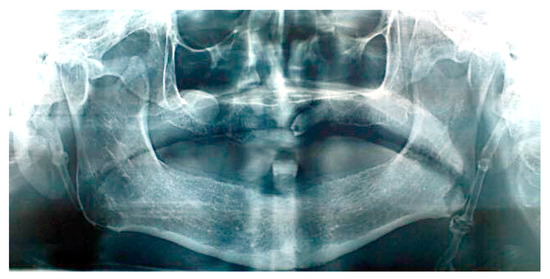

Patient #1 is categorized in the group confirming diagnosis of true Eagle’s syndrome and scheduled for surgery. After preparation for general anesthesia, surgery was performed by the extraoral trans cervical per via approach into the parapharyngeal space, for identification of styloid process, which was subsequently surgically removed for half of its length (~25 mm), seen in repeated panoramic X-ray acquisition (Figure 2).

Figure 2. Cropped panoramic image showing resected styloid process.